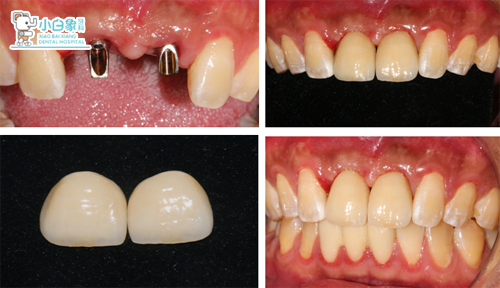

2017年10月30日 11、21硅橡胶取模,比色:2R2.5。

2017年11月24日 11、21戴牙。

2017年12月25日 11、21 修复体复查。